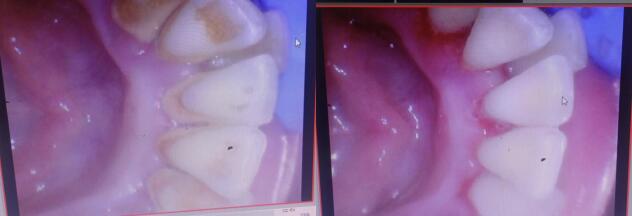

牙龈出血最常见于龈炎和牙周炎。菌斑、牙结石等刺激物堆积在牙龈缘附近,易引起牙龈红肿出血。此时的出血多出现在刷牙和进食硬物时,比如啃食苹果等,如果不重视,龈炎可能发展为牙周炎。菌斑牙结石的刺激进而引起牙槽骨吸收,将来可能出现牙齿松动、脱落等症状。并且牙结石等刺激物无法通过日常刷牙去除,需到医院进行专业的洁治、刮治,以恢复牙龈健康。